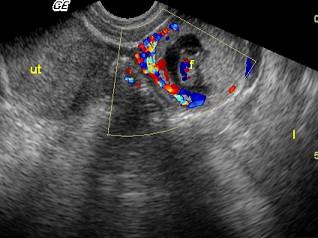

问题 女性,35岁,停经43天,阴道不规则出血一周。超声检查见图,最可能的诊断是 ( )

选项 A、黄体囊肿 B、正常声像图 C、宫外孕 D、畸胎瘤 E、炎性包块

答案 C